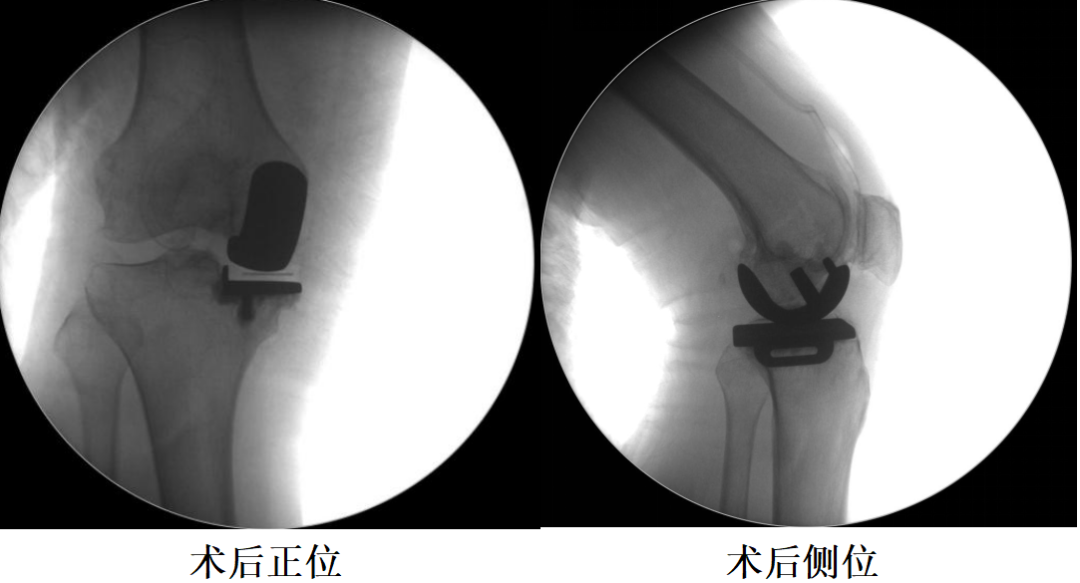

四、术后X片

第三代UKA技术:解剖型和非解剖型设计均可使用。通过机器人系统进行虚拟张力测试,并调整假体位置以最大限度地减少胫骨截骨水平。

第三代UKA技术:关节线抬高2-4毫米,同时保持理想的运动学。通常需要优先股骨截骨和缩小股骨,从而减少胫骨截骨,胫骨假体放置在致密的软骨下骨,而不是松质骨上。传统器械可能无法做到这些。